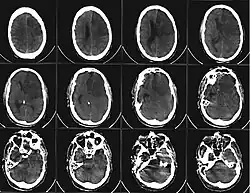

Einteilung nach Infarktmuster in der Bildgebung

Es kann zwischen Territorialinfarkten, Grenzzoneninfarkten und lakunären Infarkten unterschieden werden.

Territorialinfarkte entstehen durch embolischen Verschluss hirnversorgender Arterien und betreffen das Versorgungsgebiet (Territorium) des Gefäßes. Lakunäre Infarkte sind kleiner als 1,5 cm. Sie entstehen meist durch mikroangiopathische Veränderungen. Grenzzoneninfarkte sind hämodynamischer Genese. Sie entstehen meist durch Verschluss der großen extrakraniellen Gefäße oder durch einen passageren Blutdruckabfall bei vorbestehenden Einengungen der Halsschlagadern.[9]

Aus der oben beschriebenen Problematik ergibt sich die Dringlichkeit der raschen ärztlichen Evaluation zur potenziellen Indikation einer Lysetherapie, deren wirksames Zeitfenster allgemein als 4,5 Stunden nach Symptomeintritt angesehen wird. Auch innerhalb dieses Zeitfensters für die Anwendung von Maßnahmen, welche geeignet sind die Blutversorgung wiederherzustellen, hat sich gezeigt, dass zur Minimierung bleibender Schäden ein frühestmöglicher Therapiebeginn angestrebt werden sollte. In der Darstellung fast aller Schlaganfall-Formen haben sich moderne MRT-Geräte mit spezialisierten, perfusions-diffusions-gewichteten und anderen spezialisierten Sequenzen (FLAIR, T2*) als überlegen erwiesen, aufgrund der häufig jedoch schlechteren Verfügbarkeit bei längerer Untersuchungsdauer ist die Notfalldiagnostik bei entsprender Anamnese und klinischem Bild nach wie vor häufig das CCT. Dieses eignet sich prinzipiell zum schnellen Ausschluss der primären Kontraindikationen der Lysetherapie mit RtPA, dem Vorliegen einer intracraniellen Blutung sowie eines Hirntumors. Besonders bei unklarem Symptombeginn ist das MRT jedoch in der Lage, durch Bestimmung eines Perfusions-Diffusions-Mismatchs, also die Darstellung eines Areals, über dem die perfusionsgewichtete Bildgebung schon auffällig, die diffusionsgewichtete jedoch noch nicht auffällig ist, einen Eindruck des schon geschädigten in Relation zum noch zu schädigenden Areal (Penumbra) zu geben.[10]